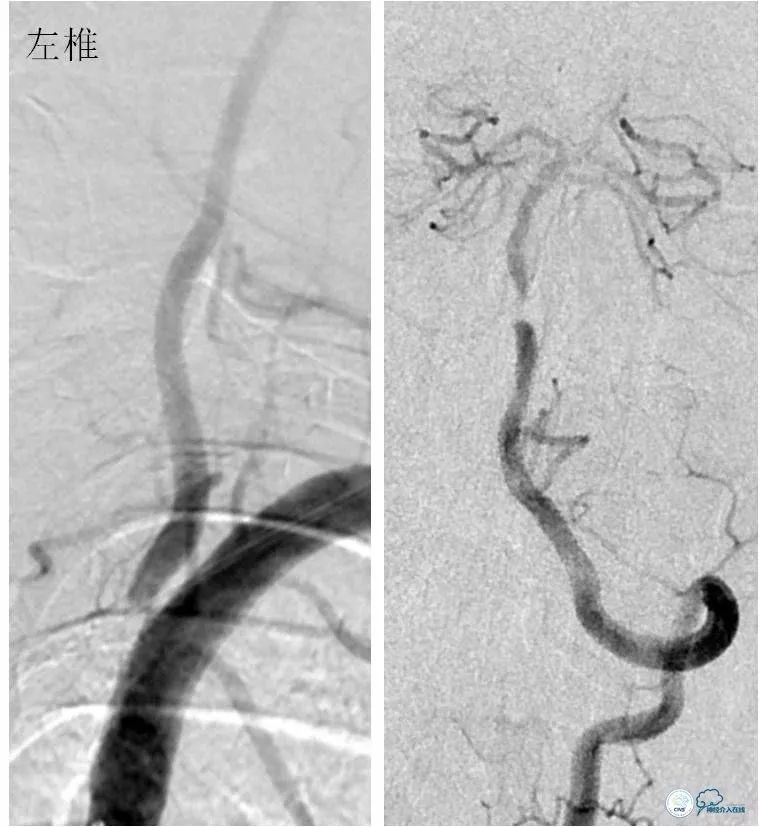

DSA:左椎动脉优势,左椎动脉V1段重度狭窄,右椎动脉V1段中度狭窄,双椎动脉V4-基底动脉下段重度狭窄,狭窄率约为85%,狭窄段有AICA发出,双侧后交通动脉未开放(图6-9)。

图6

图7

图8

图9